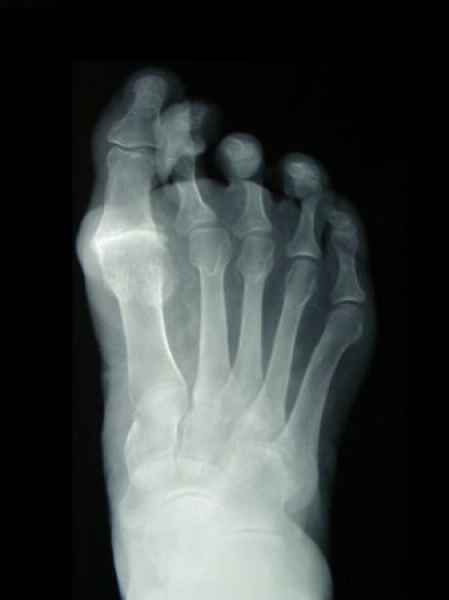

La marcha no solo es característica de la especie humana sino también de cada persona, y más aún varía según el estado de ánimo del momento. Una patología en los pies, se traduce en el rostro, en el ánimo, en el psiquismo. No sólo el dolor produce estos efectos, también un pie deformado o poco estético. En nuestra sociedad, la estética constituye un valor muy apreciado y estas alteraciones causan vergüenza fundamentalmente en las mujeres, que esconden en la playa sus pies en la arena y no pueden usar calzados elegantes.